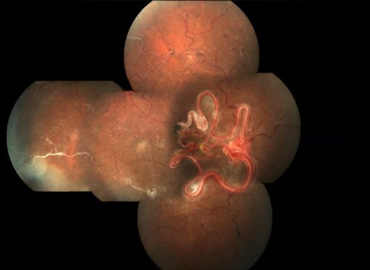

Retina Clinic (Surgical And Medical)

Main activities Medical Retina

1. Advanced center for ocular imaging

• Digital fundus photography.

• Optos wide field Photography.

• Mobile camera based telescreening.

• Fundus fluorescein angiography.

• Indocyanine angiography.

• Ultrasound B-scan.

• Ultrasound biomicroscopy.

• Laser indirect ophthalmoscopy.

• Spectral domain optical coherence tomography.

• Fundus autofluorescence imaging.

2. Retinal Electrophysiology

Surgical Retina

Dedicated retina or with wide angle retinal viewing systems (BIOM & RESIGHT). Alcon constellation-micro incision vitrectomy surgery for complicated retinal disease like diabetic retinopathy, macular hole, retinal detachment, ocular trauma, intraocular foreign bodies, Intraocular tumours.